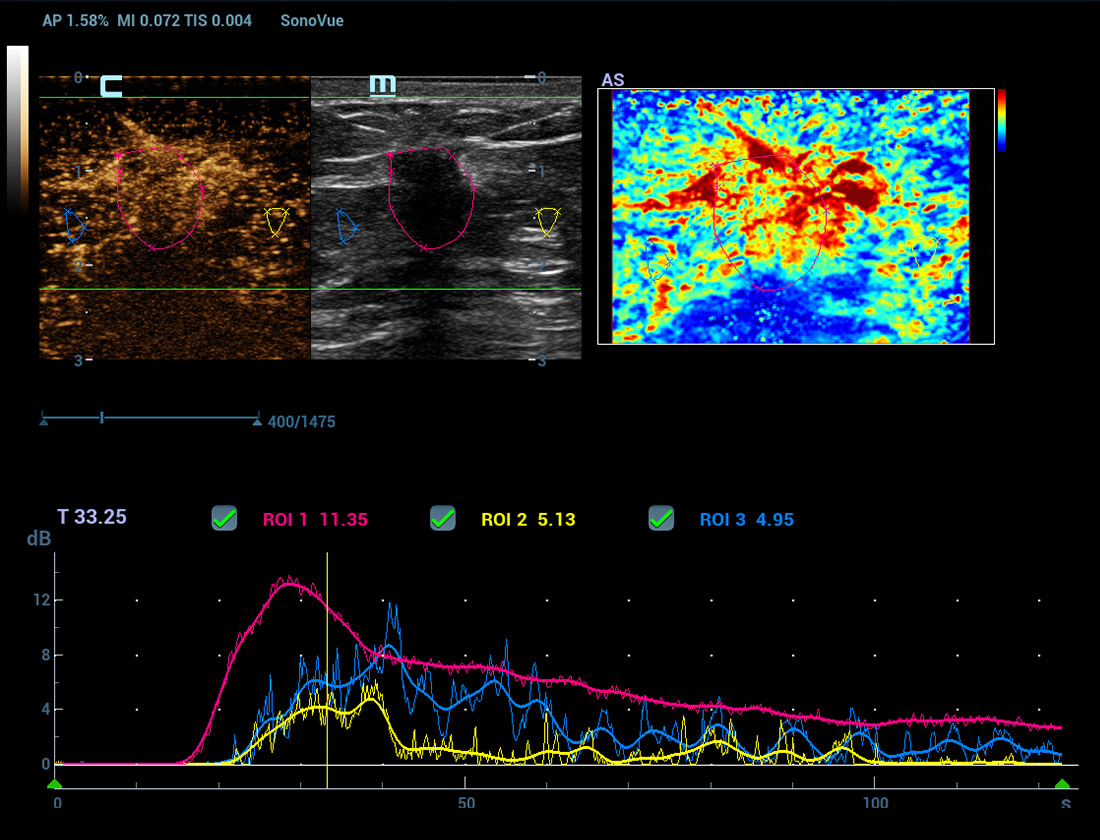

Nieuwe CEUS QA

Geavanceerde CEUS-kwantificatietools

Nieuwe CEUS-kwantificatieanalyse

Nieuwe CEUS QA Borst kwaadaardig

De tijd-intensiteitscurve maakt kwantitatieve analyse van CEUS-beeldvorming mogelijk. De nieuwe CEUS QA biedt tools voor geavanceerde kwantitatieve analyse die ondersteuning bieden bij tumorbeoordelingen en klinisch onderzoek.